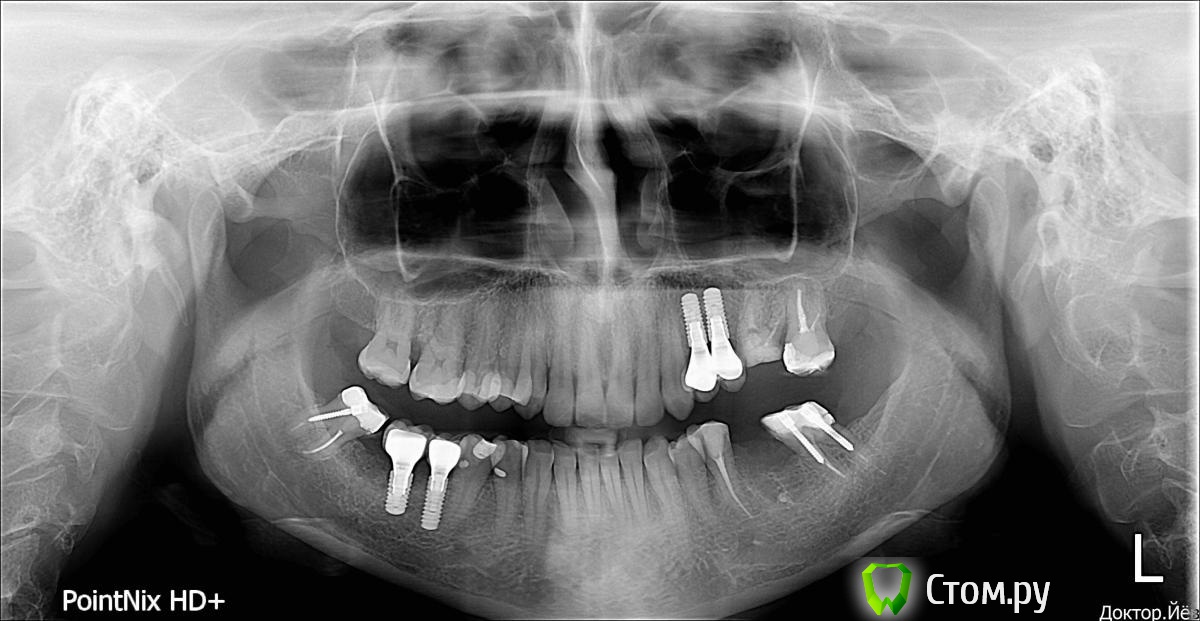

Tanya17 Опубликовано 17 декабря, 2013 Поделиться Опубликовано 17 декабря, 2013 Пожалуйста помогите определиться в ситуации. Можно ли в моем случае поставить мост внизу на место отсутствующего зуба,или придется ставить имплант? Очень бы не хотелось- я достаточно тяжело перенесла такую операцию Ссылка на комментарий

Tanya17 Опубликовано 17 декабря, 2013 Автор Поделиться Опубликовано 17 декабря, 2013 Снимок Ссылка на комментарий

Tanya17 Опубликовано 17 декабря, 2013 Автор Поделиться Опубликовано 17 декабря, 2013 Можно конечно!Просто врач, который смотрел сказал, что крайний зуб очень сильно наклонен и может не выдержать нагрузки от моста и сломаться Ссылка на комментарий

Tanya17 Опубликовано 18 декабря, 2013 Автор Поделиться Опубликовано 18 декабря, 2013 Ну ему виднее, я же во рту не видел.А по снимку оно как выглядит? Или без осмотра нельзя дать прогноз?А еще, скажите пожалуйста, нужно ли перелечивать каналы в обоих опорных зубах под мост? Ссылка на комментарий

anvladd Опубликовано 18 декабря, 2013 Поделиться Опубликовано 18 декабря, 2013 бывает на снимке одно,во рту другое.перелечивать не надо,кто то может предложить удалить штифты и сделать вкладку,я бы не стал,тк корни могут не выдержать и треснуть при удалении их. Ссылка на комментарий

Tanya17 Опубликовано 11 января, 2014 Автор Поделиться Опубликовано 11 января, 2014 Добрый день!Снова прошу помощи. Беспокоит нижний шестой имплант. Не могу понять болит он, или зуб рядом с ним.Уже обращаласьк доктору и на зубе залечили кариес. Но боль периодически возникает и по ощущениям болит именно имплант.Снова попасть к своему доктору могу только через неделю и очень беспокоюсь. Может имплант где-то нерв задевает? Ссылка на комментарий

Bier Опубликовано 11 января, 2014 Поделиться Опубликовано 11 января, 2014 нерв не задевает. Почему болит по RG не понять. Ссылка на комментарий